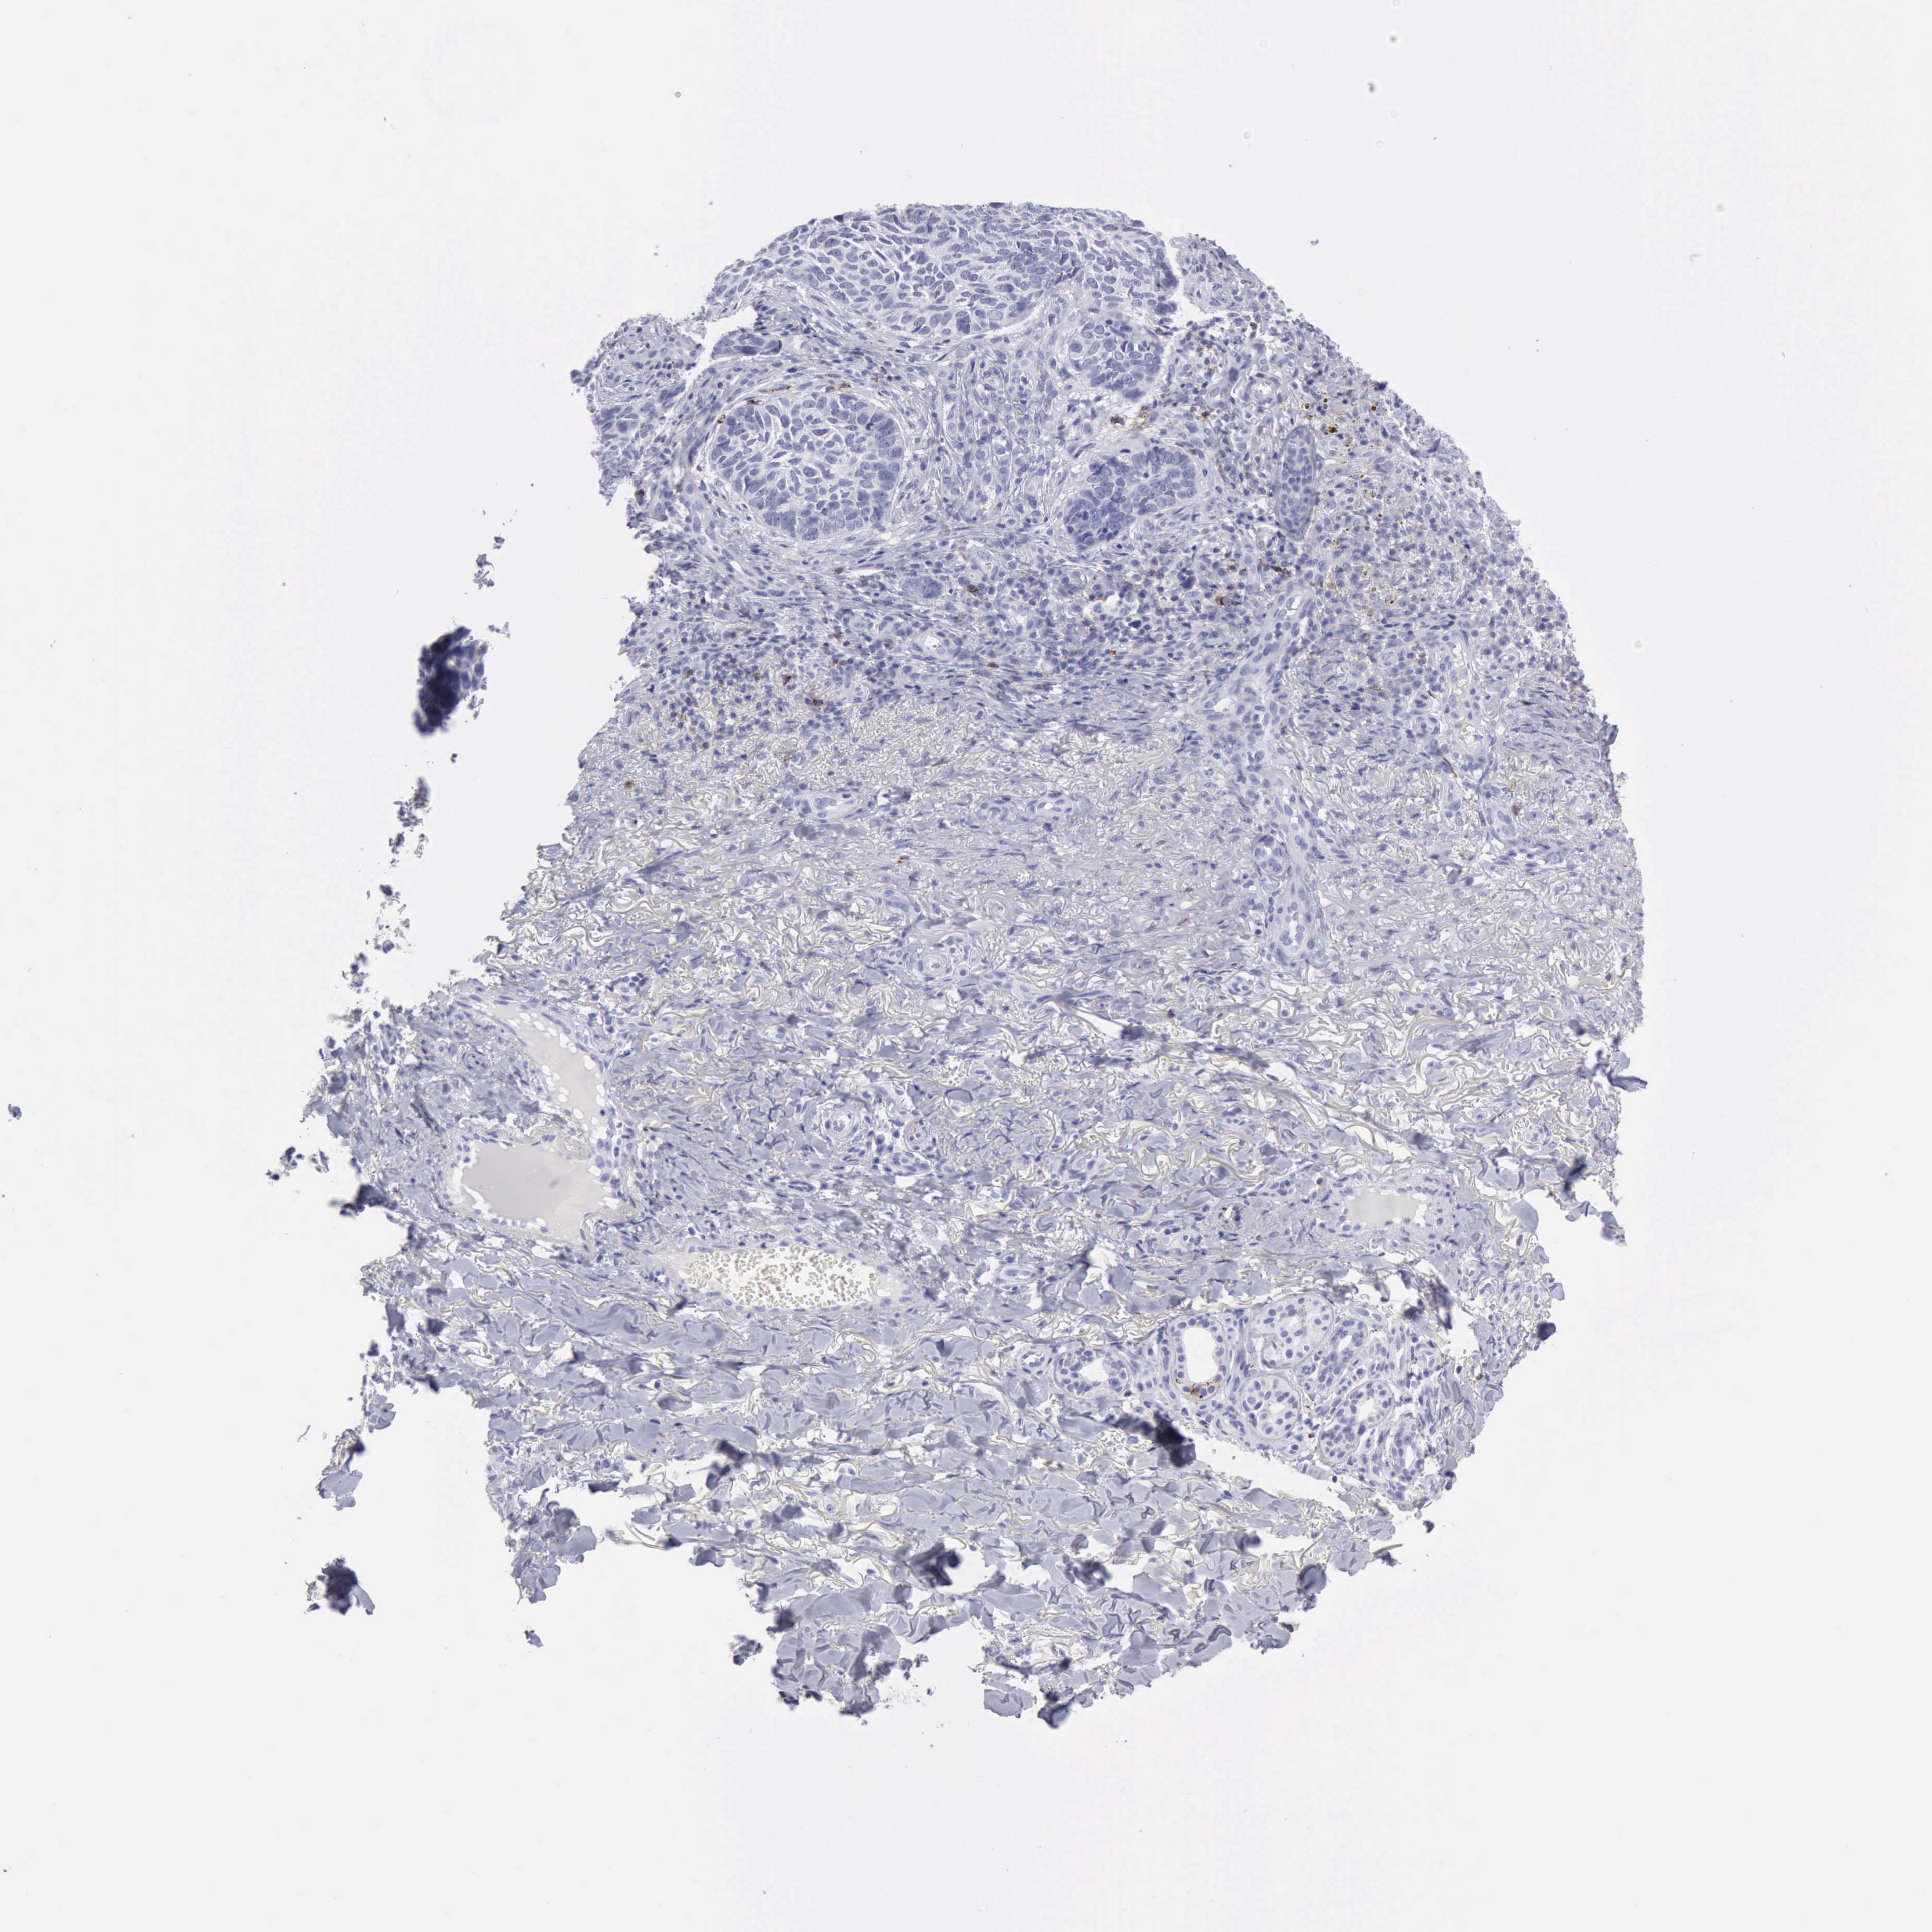

SKIN CANCER - Protein expressioni

A mouse-over function shows sample information and annotation data. Click on an image to view it in a full screen mode. Samples can be filtered based on level of antibody staining by selecting one or several of the following categories: high, medium, low and not detected. The assay and annotation is described here.

Each image is clickable and will lead to virtual microscopy that enables deeper exploration of all samples and also displays staining intensity scores, fraction scores and subcellular localization as well as patient and tissue information for each sample.

Antibody HPA039835

Antibody CAB000142

Antibody CAB018071

Basal cell carcinoma

Squamous cell carcinoma, NOS

Squamous cell carcinoma, metastatic, NOS

Squamous cell carcinoma in situ, NOS

Adnexal tumor, benign